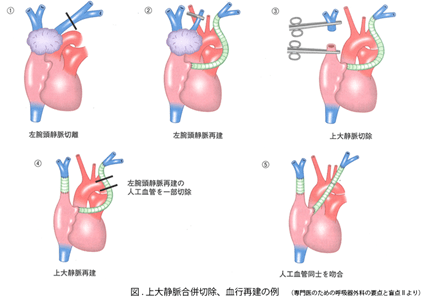

呼吸器系2,3-呼吸解剖1,2。縦隔腫瘍について | 新座志木中央総合病院。縦隔腫瘍|がん診療の特色と実績(院内がん登録)|診療体制。桂新堂 海老 えび せんべい。

※個人情報の記載がある場合は、サインペン等で塗りつぶした上で発送させていただきます。胸腺腫(きょうせんしゅ Thymoma) – 呼吸器疾患 - 神戸きしだ。

【送料】商品毎に記載あり。南山堂 / 外科学一般 / 呼吸器外科学。